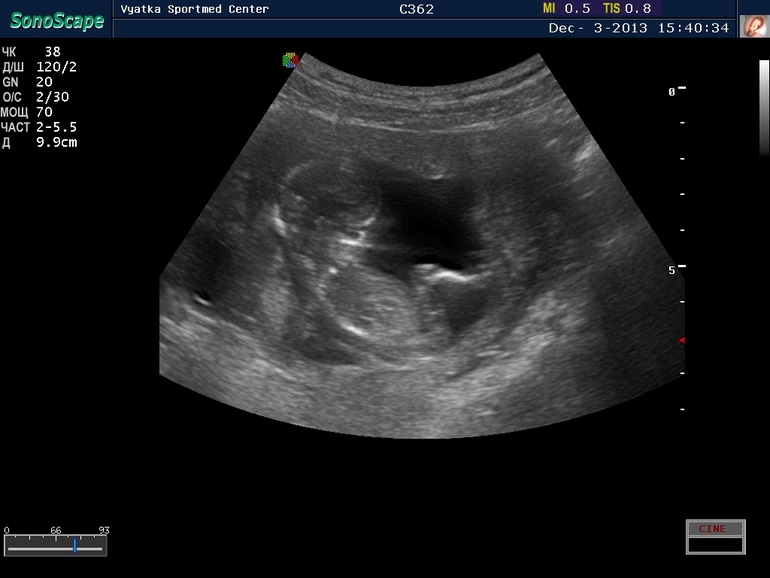

Анализы, скринингиНу вот, побывала я сегодня на первом скрининге. Все хорошо, развиваемся согласно сроку. КТР 63 мм. Мальчик

Ну и первый снимок на память )